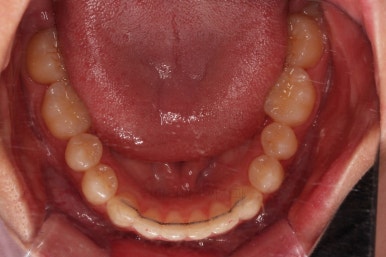

치료가 1년만에 종료가 되었네요.

치아가 가지런해졌고, 교합이 잘 맞는 모습이에요.

치열의 모습이 좋아졌고, 웃을 때 보이는 치열이 가지런해서 미소도 훨씬 예뻐졌네요.

옆라인이라던지 입을 다물었을 때의 느낌은 원래도 좋으셨기 때문에 거의 그대로 유지가 되었고요.

1년정도 만의 만족스러운 치료였습니다.

이상 비발치로 덧니와 삐뚤한 앞니를 교정치료한 치료사례였습니다.